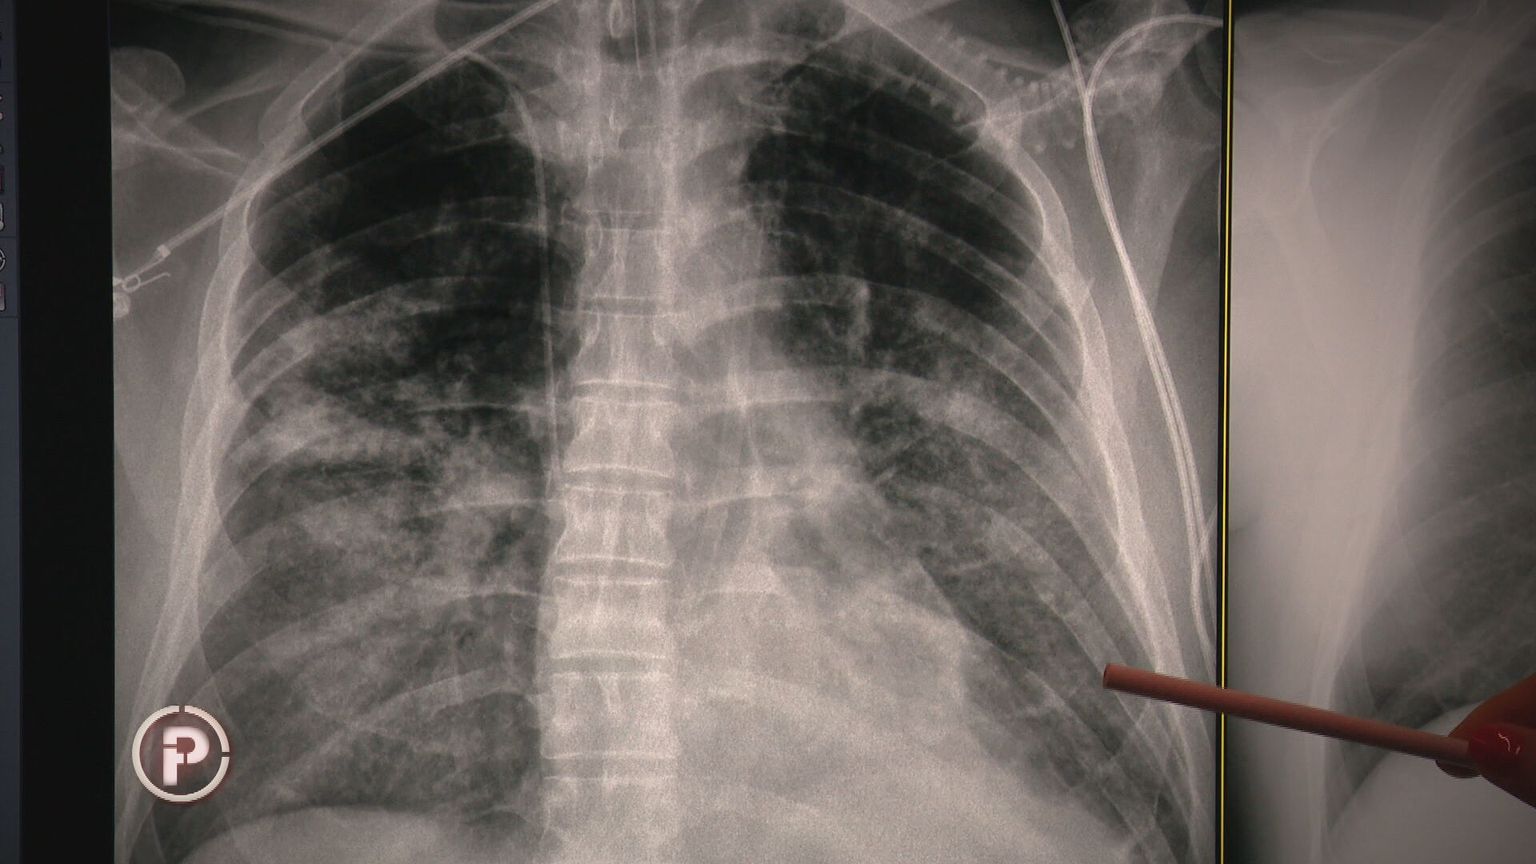

• Pluća Foto: Provjereno